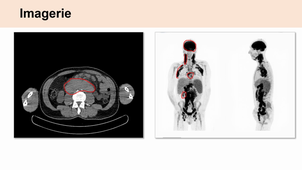

Lymphomes